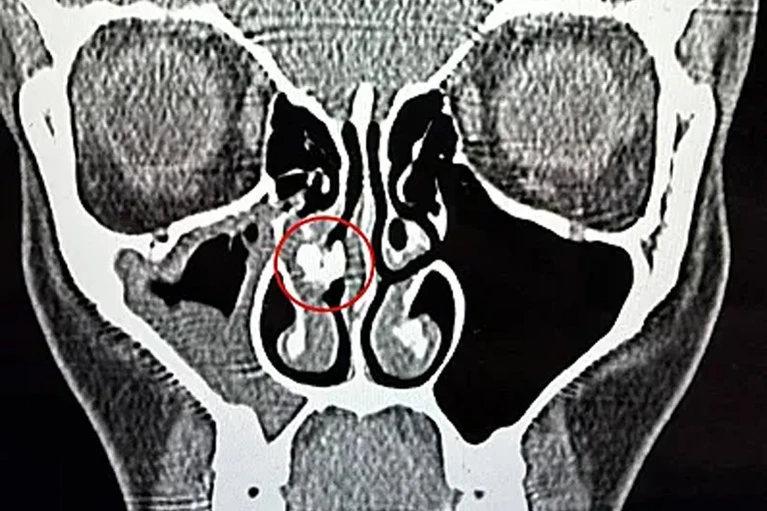

Переломным моментом стал 2025 год, когда женщина обратилась в больницу с синуситом. После компьютерной томографии врачи выявили в её носовой полости инородное тело. Спустя час его извлекли пинцетом — им оказался кусок клейкой ленты. Рейбо показала находку в TikTok и призналась, что не понимает, как скотч оказался в её носу и сколько времени он там находился.